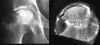

**COULD SHOW ON BOARD!** What is this a picture of?

Osteosarcoma arising in Paget disease! 1% of patients with Paget disease will develop osteosarcoma You can tell this is arising in Paget because of the mosaic lines (changing direction) in the bone